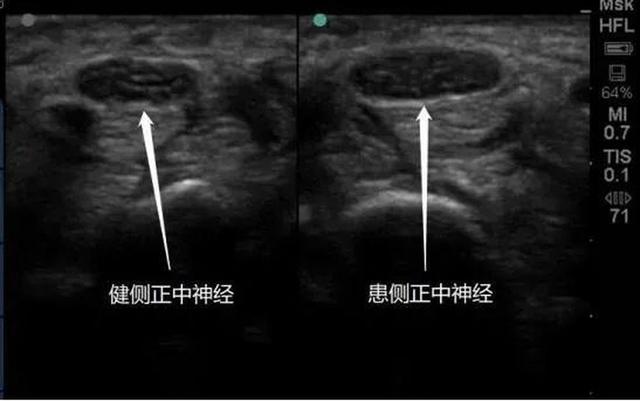

腕管综合征,俗称“鼠标手”,是由于长时间使用鼠标和键盘而引发的手部疾病,发病率在现代社会正逐年上升。这一病症的主要症状包括手腕疼痛、手指麻木、无力等,严重时甚至会影响手部的正常功能,给患者的日常生活和工作带来极大的困扰。在过去,由于缺乏对这一病症的足够认识和重视,许多劳动者在患上腕管综合征后,其健康权益并未得到充分保障。